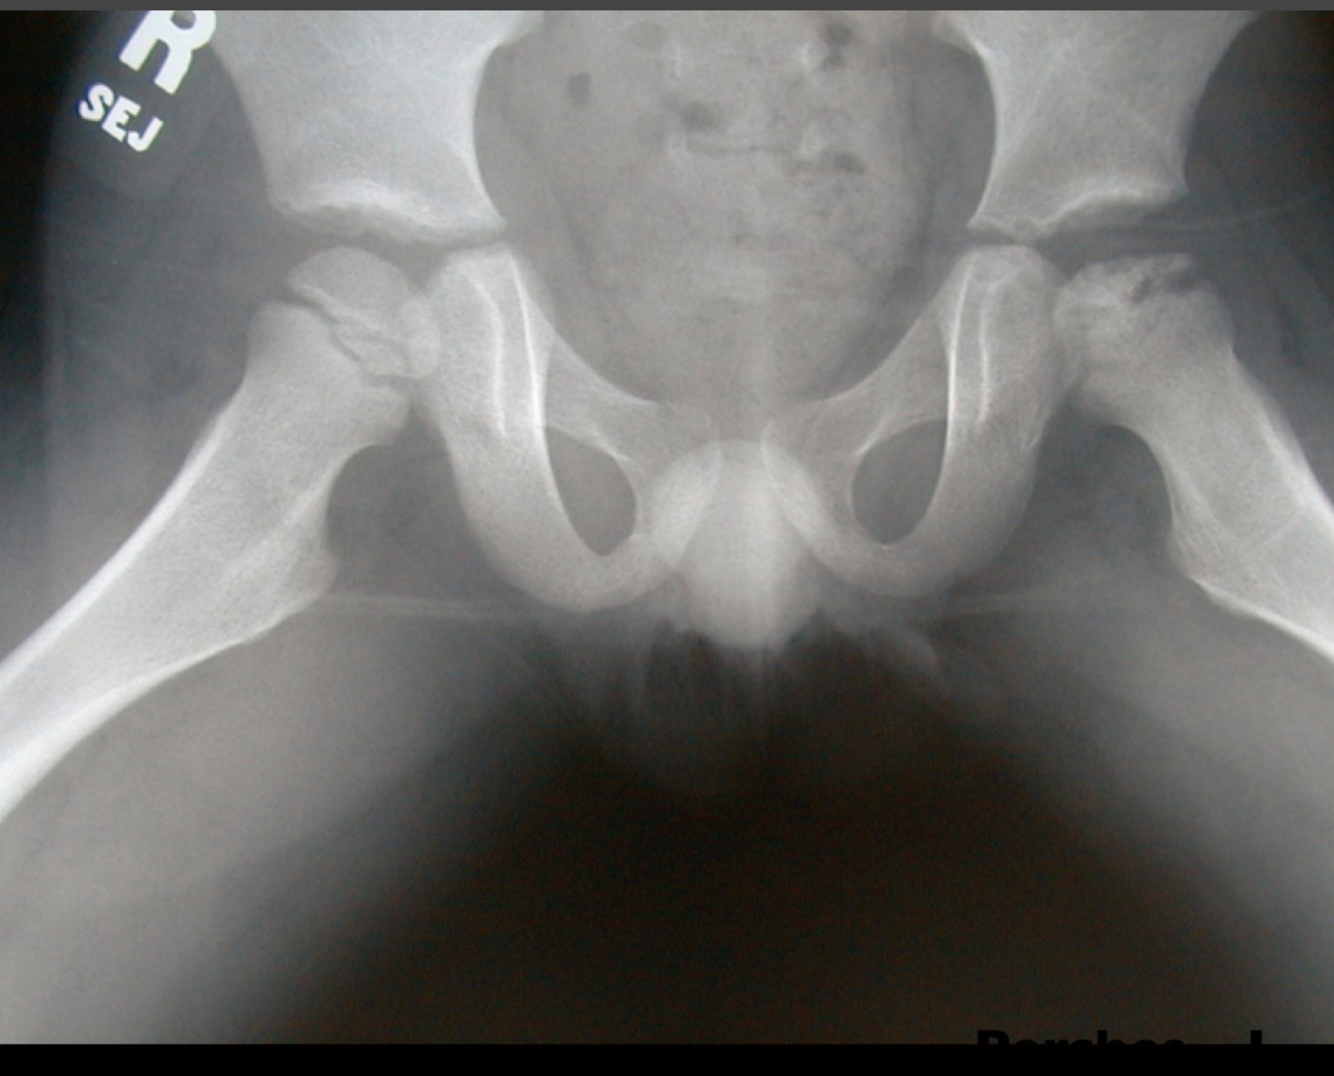

Perthes